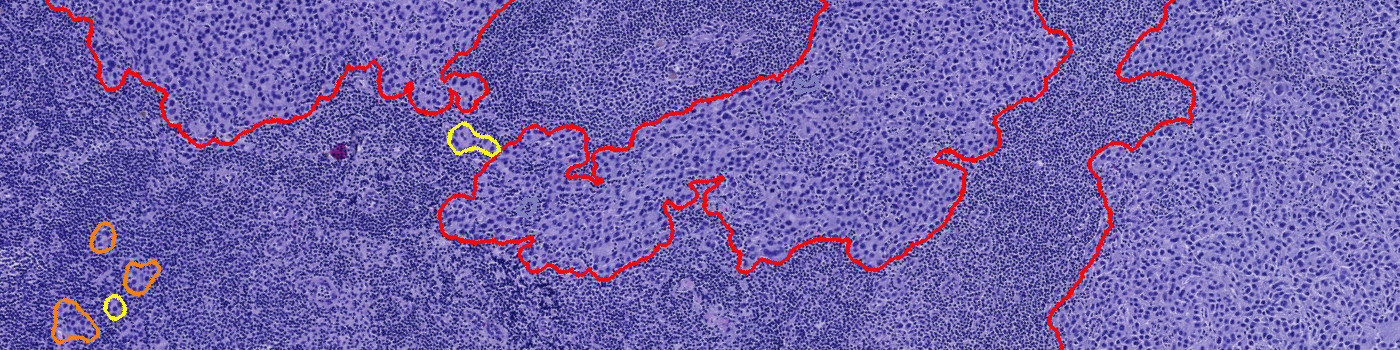

Step 2: Metastasis Detection: Identifies possible metastases using AI.

Step 3: Post Processing: Post-processes the classification results, improving accuracy and visualization.

Step 4: Calculate Results: Locates the single largest metastasis and calculates the diameter and/or calculates the total metastasis area.